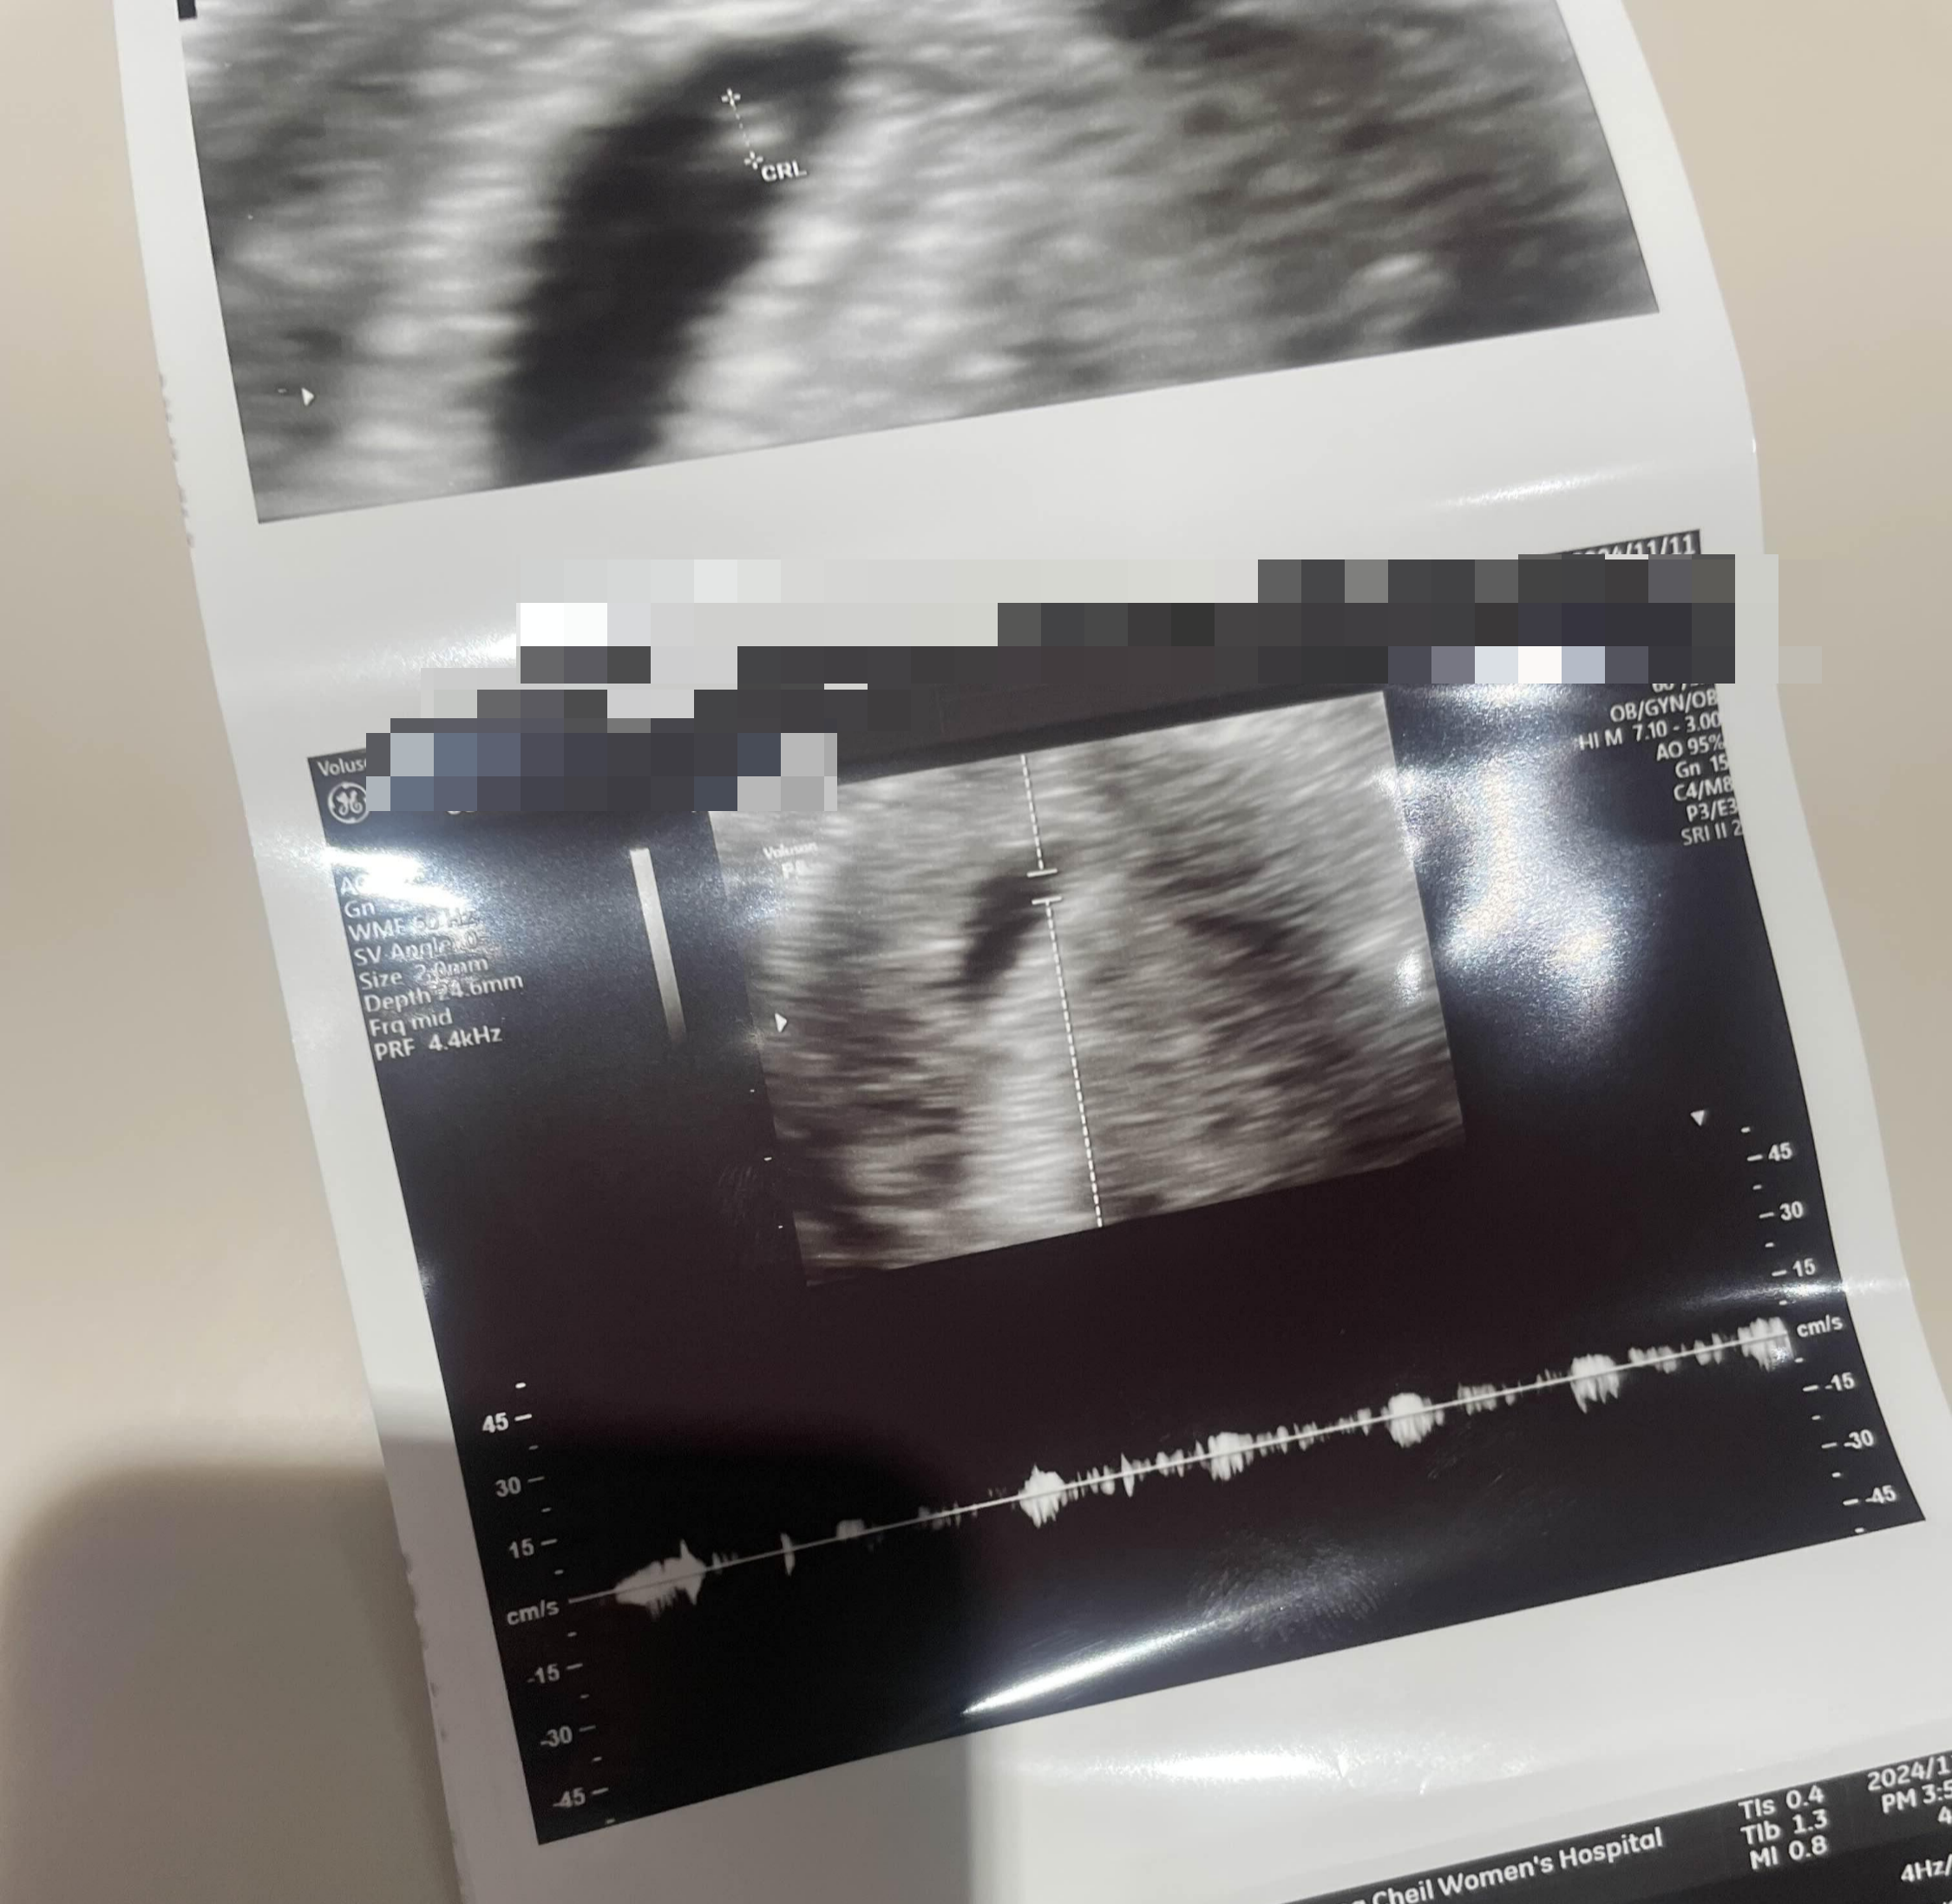

자세히 보니 남들처럼 울 아기도 콩짝콩짝 하고 심장이 뛰는거 까지 보였다.

반지모양 난황도 보이고 캐슈넌 모양 아기도 있다.

배 초음파 마무리하고 직접 심장소리 함 들어보자시며

질초음파로 진행했는데 확실히 더 선명하게 보였다.

너무 작은 우리애기 ... 💕

심장소리도 들었는데 쿵쾅쿵쾅 아주 잘 뛰고 있고

간격도 아주 훌륭하다고 하셨다.

아참 그리고 주수는 5주 6일차라고 한다.